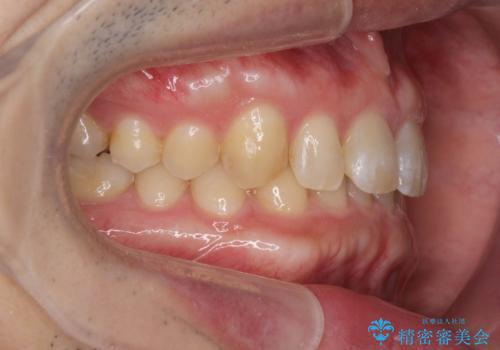

ディープバイトのマウスピース矯正

- 飛び出してしまい、隙間のある前歯をきれいに並べたい、と矯正治療を希望され来院されました。

上顎前歯を後方に引き、隙間を閉じるためには下顎前歯の絶対的な圧下を行い、深い噛み合わせを改善することが必要です。

前歯でチューイーをしっかり噛み、咬合圧を伝えたことで下顎前歯が圧下し、上顎前歯の隙間を閉じることができました。